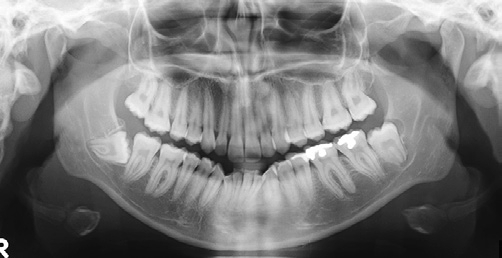

Die Patientin stellte sich im Alter von 23 Jahren zu einer kieferorthopädischen Beratung vor. Sie störten die Engstände im Unterkieferzahnbogen. Die extraoralen Aufnahmen zeigen ein schönes, harmonisches, leicht konvexes Profil, das nach den Grundregeln der Ästhetik nicht verändert werden darf (Abb. 18a bis c). Die intraoralen Aufnahmen zeigten zu Behandlungsbeginn eine Angle-Klasse-I-Okklusion, Tendenz zu Klasse III rechts und Klasse I links. Auf der Frontalaufnahme ist die knappe sagittale und vertikale Frontzahnstufe zu sehen (Abb. 19a bis c). Im Rahmen der Modellanalyse konnte eine harmonische Breitenrelation beider Zahnbögen im Bereich der Molaren und Prämolaren ermittelt werden, im Oberkiefer waren die Platzverhältnisse ausgeglichen. Im Unterkiefer lag ein Engstand von insgesamt 5 mm vor, wobei sich die Engstände auf die Frontzahnregion konzentrierten (Abb. 19d und e). Das angefertigte OPG (Abb. 20) zeigte, dass alle Zähne vorhanden und die Zähne 38 und 48 retiniert und verlagert waren. Im Seitenzahngebiet war eine konservierende Versorgung zu verzeichnen. Die parodontale Situation war röntgenologisch sowie klinisch unauffällig und die Knochenverhältnisse ließen eine orthodontische Behandlung zu. Die Fernröntgenaufnahme (Abb. 21) zeigte keine skelettalen Auffälligkeiten. Die Oberkieferfront stand nahezu achsengerecht, die Unterkieferfront war nach labial gekippt (Tab. 3).